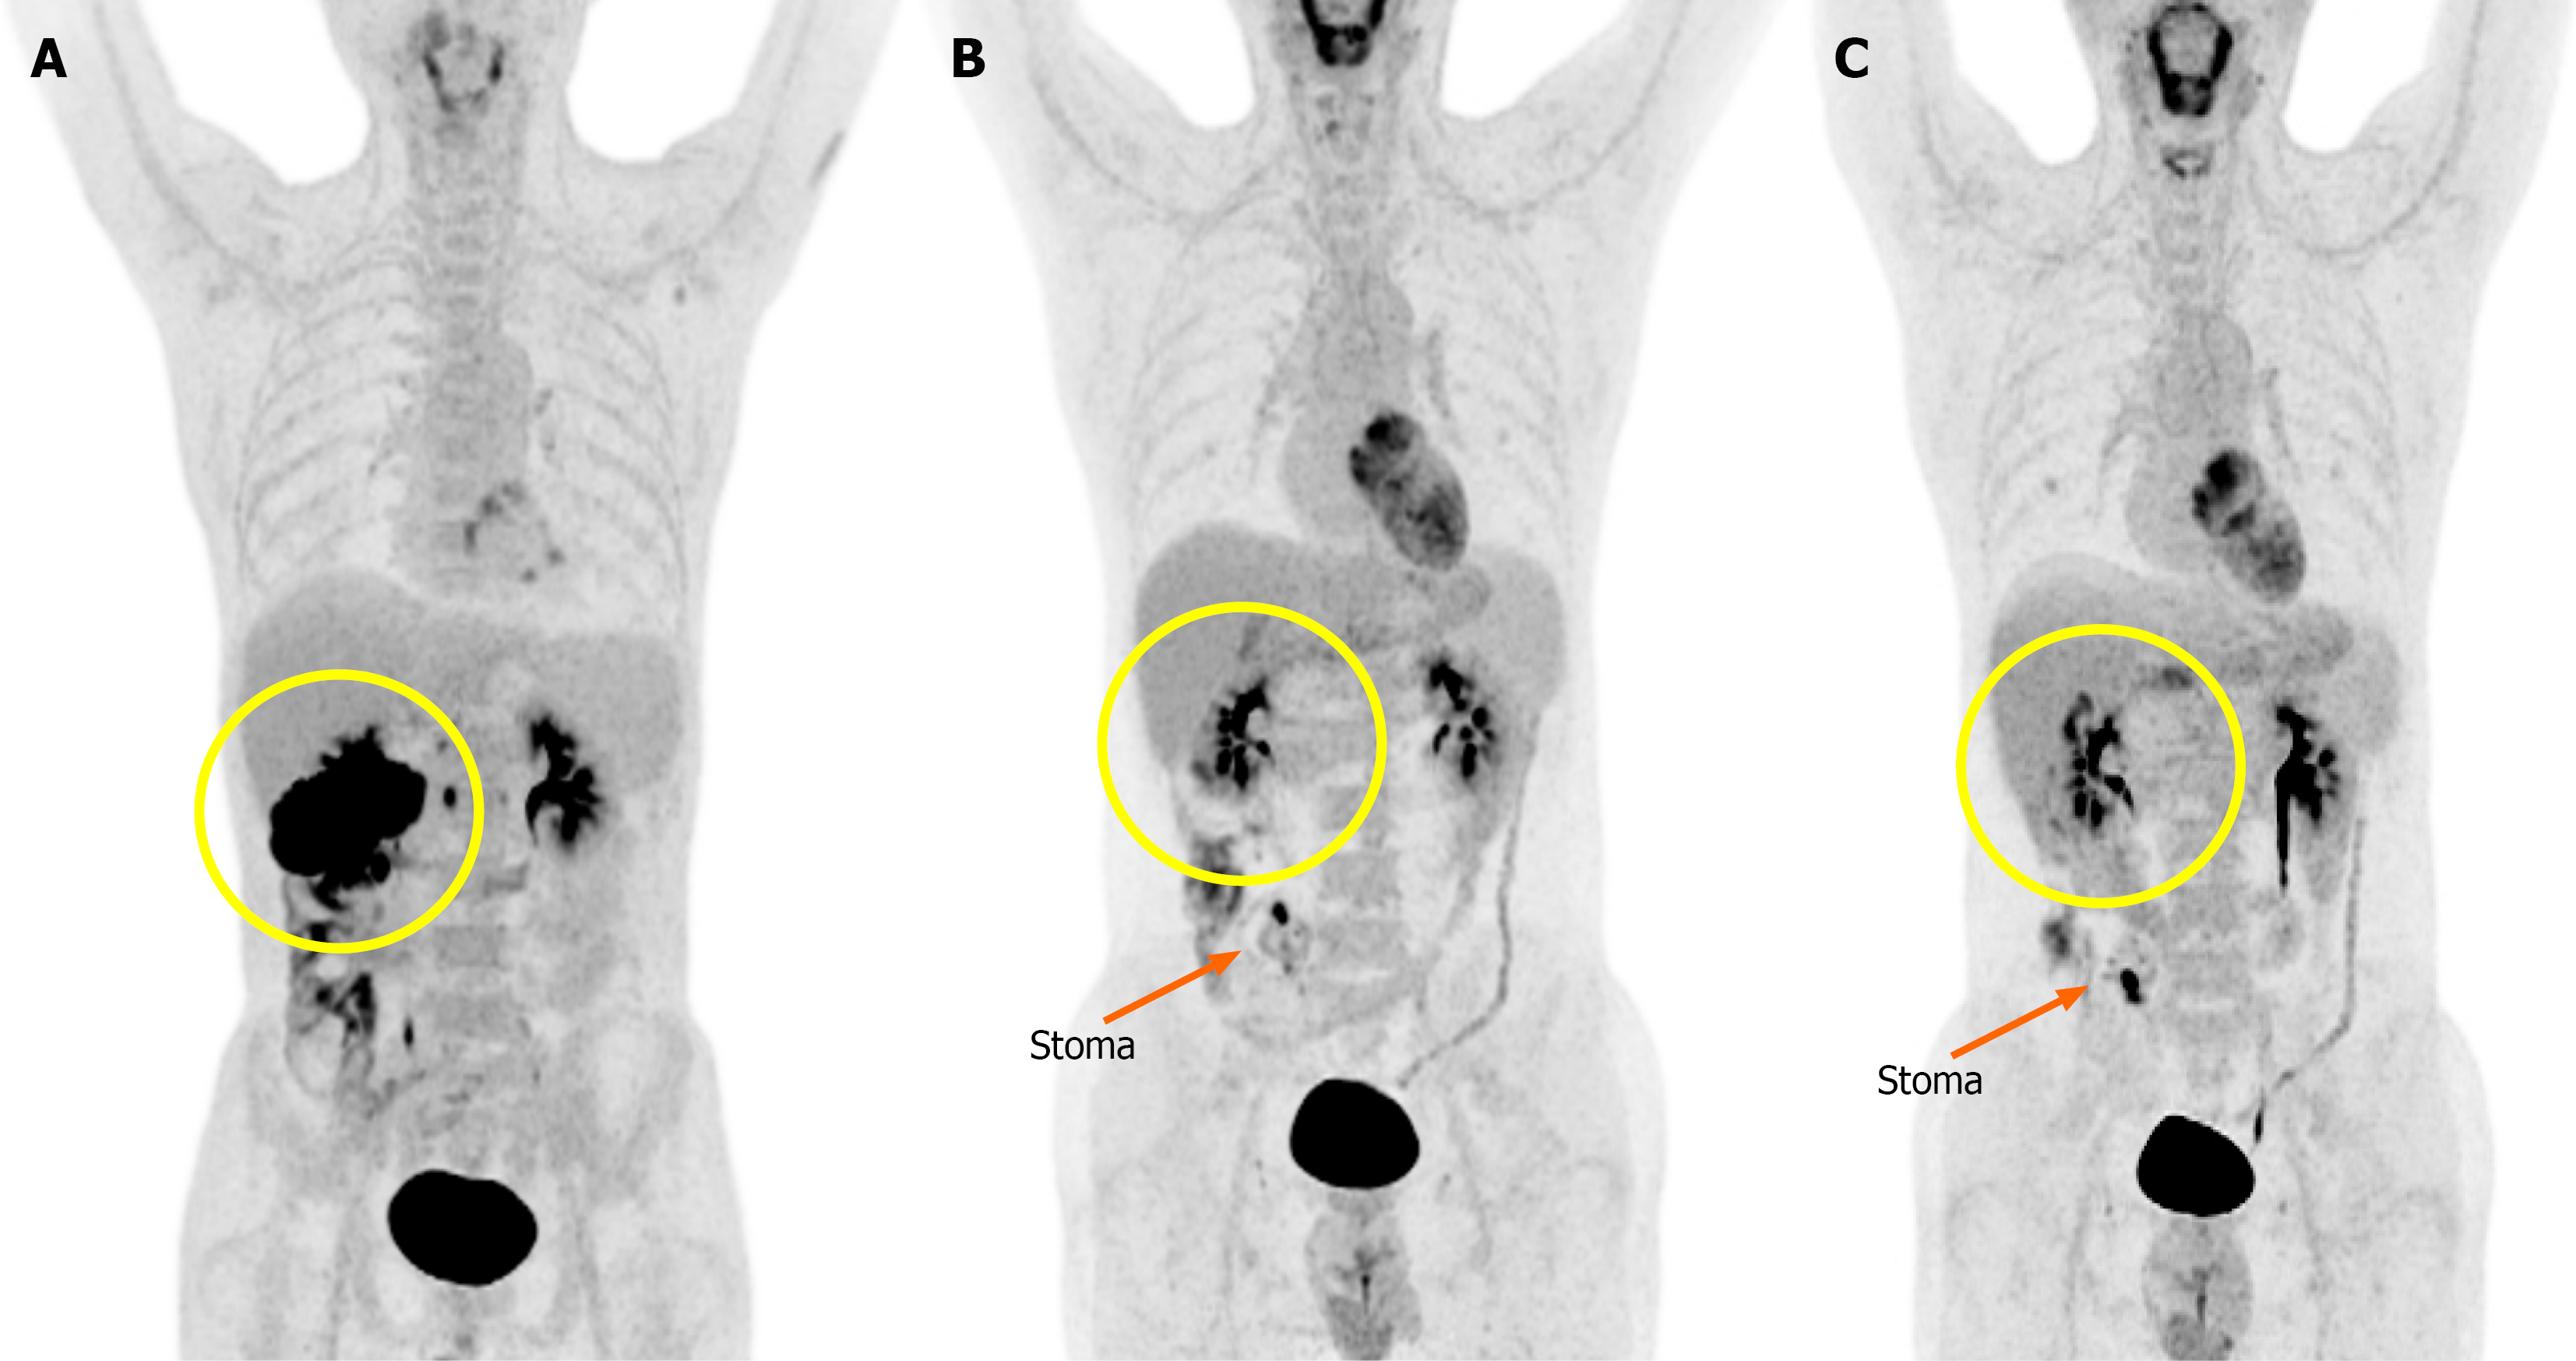

Figure 1 Serial fluorodeoxyglucose positron emission tomography-computed tomography.

A: Baseline imaging showed intense fluorodeoxyglucose uptake in the hepatic flexure of the colon, multiple hypermetabolic liver lesions, and suspected peritoneal involvement; B: After 7 months of pembrolizumab treatment, a marked reduction in fluorodeoxyglucose uptake at the primary site and metastatic lesions was observed, indicating a significant treatment response; C: After completion of pembrolizumab treatment, complete resolution of prior hypermetabolic activity at the primary tumor site was observed. A new focal uptake was seen near the stoma and gallbladder bed, suggestive of either post-treatment inflammation or possible recurrence. The primary tumor site is marked with a yellow circle, and the stoma location is indicated by a orange arrow.